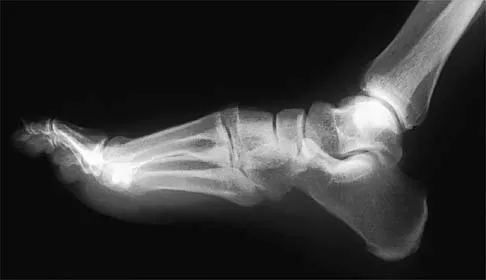

A 28-year-old professional dancer reports a 3-month history of progressive pain in the posterior aspect of the left ankle. Her symptoms are worse when she assumes the en pointe position. Examination reveals tenderness to palpation at the posterolateral aspect of the ankle posterior to the peroneal tendons which is made worse with passive plantar flexion. There is no nodularity, fluctuance, or tenderness of the Achilles tendon. The neurovascular examination is unremarkable. A lateral radiograph and MRI scan are shown in Figures 16a and 16b, respectively. Management should consist of

The imaging studies reveal findings typical of the os trigonum syndrome. This condition results from inflammation between the os trigonum and the adjacent talus. The symptoms of posterior ankle pain are exacerbated by plantar flexion, which stresses the fibrous union between these two bones. Definitive management of the high-level athlete involves excision of the os trigonum from a medial approach, although arthroscopic excision has also been described. The os trigonum is not an intra-articular structure; therefore, ankle arthroscopy is neither diagnostic nor therapeutic. Abramowitz Y, Wollstein R, Barzilay Y, et al: Outcome of resection of a symptomatic os trigonum. J Bone Joint Surg Am 2003;85:1051-1057. Mouhsine E, Crevoisier X, Leyvraz P, et al: Post-traumatic overload or acute syndrome of the os trigonum: A possible cause of posterior ankle impingement. Knee Surg Sports Traumatol Arthrosc 2004;12:250-253.